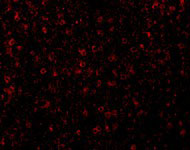

Immunofluorescence of CCR3 in Human Spleen tissue with CCR3 antibody at 20 μg/mL. |